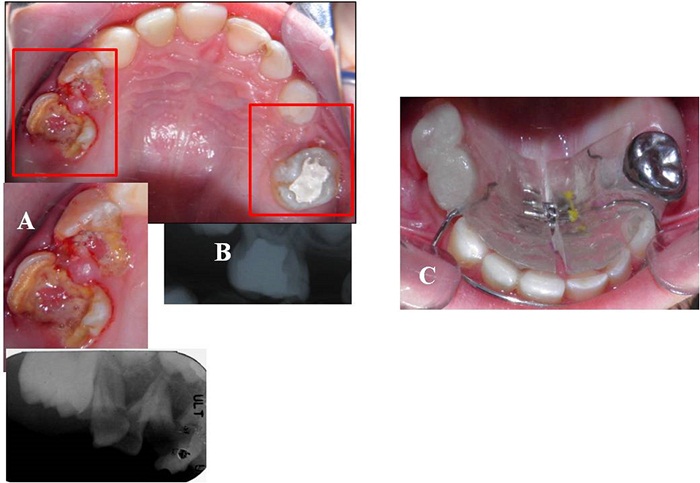

Durante la anamnesis, la madre refirió que el niño sufría desde los 2 años de edad de episodios repetitivos de broncoespasmo. Durante el examen de la cavidad oral, se observaron labios hipodróticos, mucosas humectadas, frenillos bien implantados, paladar normal, lengua saburral, piso de boca permeable y periodonto sano. El paciente presentaba caries en 11 dientes e higiene bucal deficiente. El estudio radiográfico mostró caries de diversos grados, particularmente, una lesión cariosa extensa que no permitía una correcta restauración en el segundo molar inferior derecho temporal y una fractura de la furca radicular en el segundo molar inferior izquierdo temporal (figura 2).

El plan de tratamiento se llevó a cabo por cuadrantes, en orden de prioridad. Al paciente se le rehabilitó el maxilar superior, como puede apreciarse en la figura 3, mediante exodoncia, tratamiento pulpar (pulpotomías y pulpectomías) y restauración con coronas de acero y acetato en el sector anterior (figura 4).

Para la elaboración del mantenedor de espacio se realizó una impresión con alginato en la arcada superior. Posteriormente, sobre el modelo en yeso, se diseñó un mantenedor de espacio removible sin flancos vestibulares y tornillo medio, para acompañar el crecimiento del maxilar. En el arco inferior se hicieron las exodoncias de los segundos molares, la pulpotomía del primer molar inferior derecho, con la adaptación de la corona de acero que se utilizaría como pilar del zapato distal derecho, y una restauración con resina en el primer molar izquierdo (figuras 5a y 5b). Antes de confeccionar los zapatos distales, se adaptaron la corona de acero en el primer molar inferior derecho y una banda con tubo en el primer molar inferior izquierdo (figuras 5c y 5d).